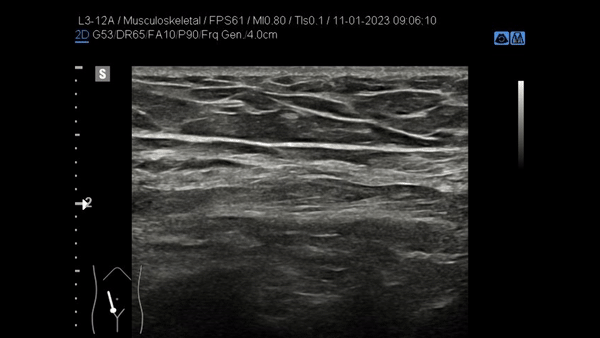

Afbeelding voor nieuwsbericht refreshment buikwand

Donderdagavond, heb ik een Refreshment gehouden in het Medisch Centrum Leeuwarden. Onderwerp was de buikwand waarin we alle mogelijke herniaties belicht hebben. Daarnaast hebben we ook stil gestaan bij andere pathologie van de buikwand. Middels anatomie en een live-demo is de onderzoeksmethode van de buikwand gepresenteerd en hebben we vervolgens geoefend in een hands-on sessie. Leuk om met collega’s uit verschillende ziekenhuizen bezig te zijn en alles rondom dit onderwerp op te frissen.